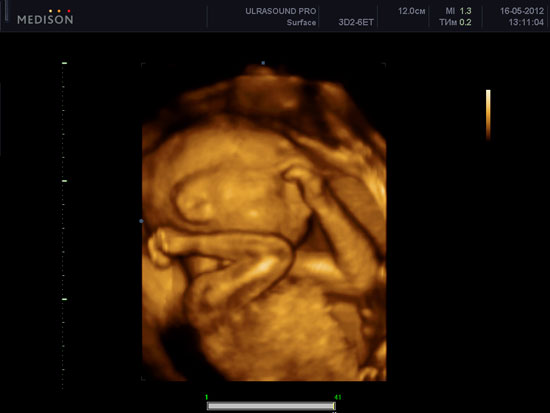

3-D УЗИ при беременности. Его цена и основные преимущества

Сегодня узи – это одно из самых важных исследований, которое проводится во время беременности. Прогресс не стоит на месте, и если раньше можно было...